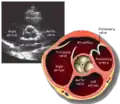

Transthoracic echocardiogram

Purposestill/moving image of internal parts of heart

A transthoracic echocardiogram (TTE) is the most common type of echocardiogram, which is a still or moving image of the internal parts of the heart using ultrasound. In this case, the probe (or ultrasonic transducer) is placed on the chest or abdomen of the subject to get various views of the heart. It is used as a non-invasive assessment of the overall health of the heart, including a patient's heart valves and degree of heart muscle contraction (an indicator of the ejection fraction). The images are displayed on a monitor for real-time viewing and then recorded.

A TTE is a clinical tool to evaluate the structure and function of the heart. All four chambers and all four valves can be assessed by TTE, but the quality and visibility of these structures varies from person to person. Other structures visible on TTE include the aorta, the pericardium, pleural effusions, ascites, and inferior vena cava. It can be used to diagnose a heart attack, enlargement/hypertrophy of the heart, infiltration of the heart from an abnormal substance (e.g. amyloidosis), weakness of the heart, and cardiac tumors. With advanced measurements of the movement of the tissue with time (Tissue Doppler), it can measure diastolic function, fluid status,[1] and ventricular dyssynchrony.